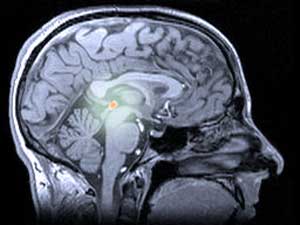

在人类和其他动物中,褪黑素由 松果体(发音为“派-尼尔”)产生,松果体是大脑深处一个略显神秘的结构。松果体有时被称为“第三只眼”,因为在一些蜥蜴中,它位于头部顶部,用于探测飞行捕食者的阴影。